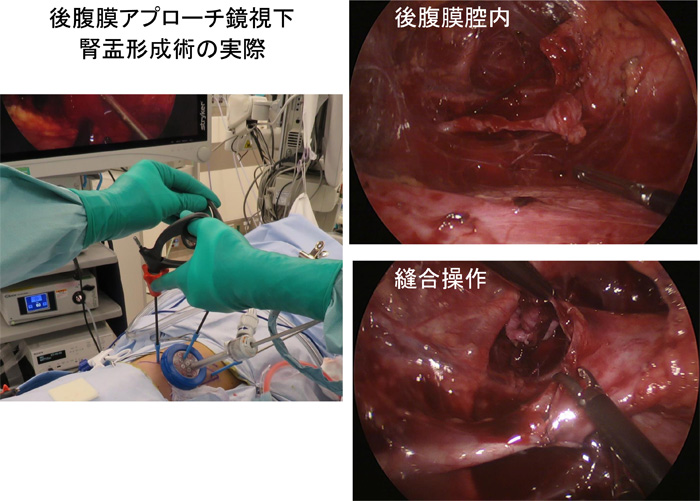

後腹膜鏡下腎盂形成術

・鏡視下腎盂形成術において、後腹膜アプローチは腹腔内操作がないため腹部内臓器関連合併症を回避できる

・従来の後腹膜開放の術式と同じ視野で同じクオリティーを保つこと ができ、開放手術へ変更を必要としたとき体位変換を行うことなくへ変更が可能

・体格の小さい乳児症例や癒着の危惧される再手術症例においても、工夫を加えることにより後腹膜鏡下で確実に安全に施行できる

・馬蹄腎合併症例の腎盂形成術でも従来の開放手術と同様に後腹膜アプローチで視野確保、吻合操作が可能である

乳児症例

馬蹄腎症例 :幼児、右側腎

後腹膜鏡下手術の実際

オリエンテーション

開放手術での経験と同じであり、創直下に直接腎へと到達できオリエンテーションが困難となることは少ない

術野スペース

手技的にUPJ周囲の剥離操作と同部位での吻合操作の みであり、運針の可能なスペースの確保のため開放手術 より少ない剥離範囲で手術可能となる利点がある

アルノート®ラップシングルを使用することで体格の小さ い症例でも鉗子操作スペースの確保ができる